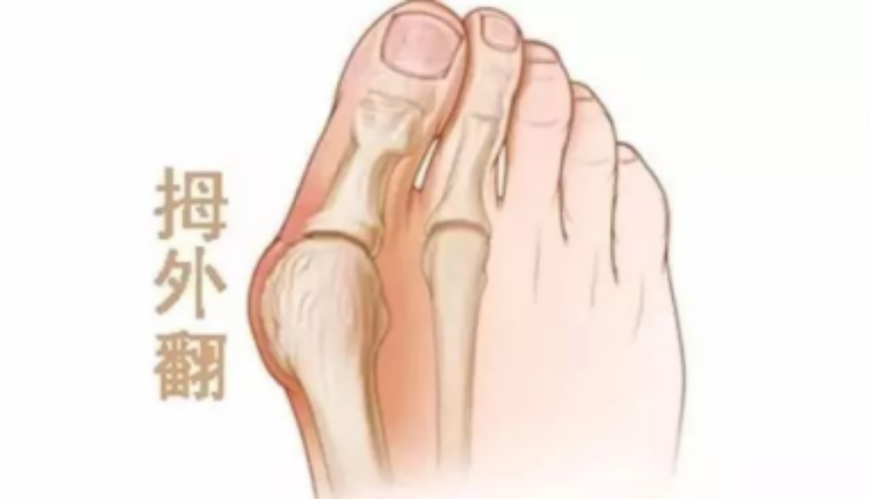

这都是“拇外翻”惹的祸。

拇外翻,俗称大脚骨,多发于女性,是大脚趾向外明显倾斜,超过正常生理范围的一种足部畸形,常常伴随红肿、疼痛等症状。

具体表现为:

大拇趾关节内侧突起,表面红肿,按压有疼痛感,穿鞋挤压后明显。

大拇趾外翻,不断挤压第二趾。